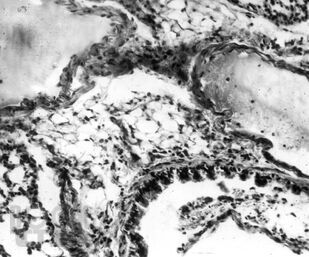

Книга посвящена вопросу лечения пелоидами очень распространенной патологии – болезней органов дыхания: острой пневмонии, хронического бронхита, бронхиальной астмы. В эксперименте и на клиническом материале показано воздействие грязелечения на воспалительный процесс, состояние иммунитета и адаптации, бронхиальную проходимость. Дана эффективность назначения иловых сульфидных, сапропелевых грязей и торфов у больных с болезнями органов дыхания. Рассмотрены вопросы переносимости этими больными грязелечения и возможности оптимизации его результатов. Приведены материалы по использованию средства «Тонус плюс», сочетающего в себе биологически активные компоненты двух видов грязей, набора трав и солевых носителей. Книга предназначена для физиотерапевтов, курортологов, пульмонологов, врачей общей практики. Это первый обобщенный труд по использованию грязелечения в пульмонологии. Его данные могут быть использованы не только в практической работе врачей, но и в учебном процессе при подготовке физиотерапевтов и курортологов.